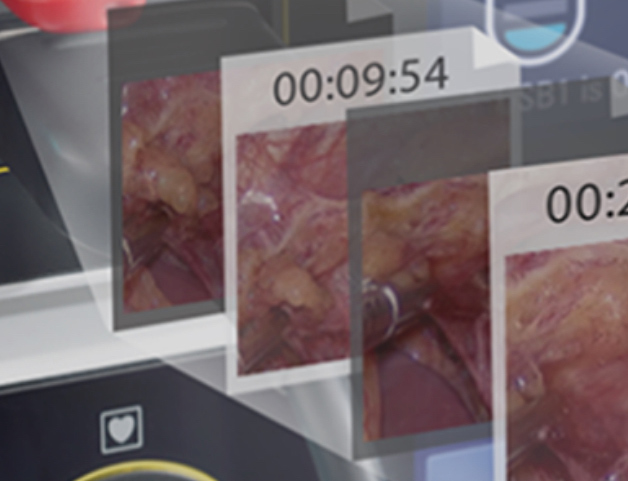

Built-in USB Recording

The built-in USB recording starts with one click, and the high-quality video will be saved as Full HD version as predefined.

With bookmark function, it is convenient for video record review and post-editing.